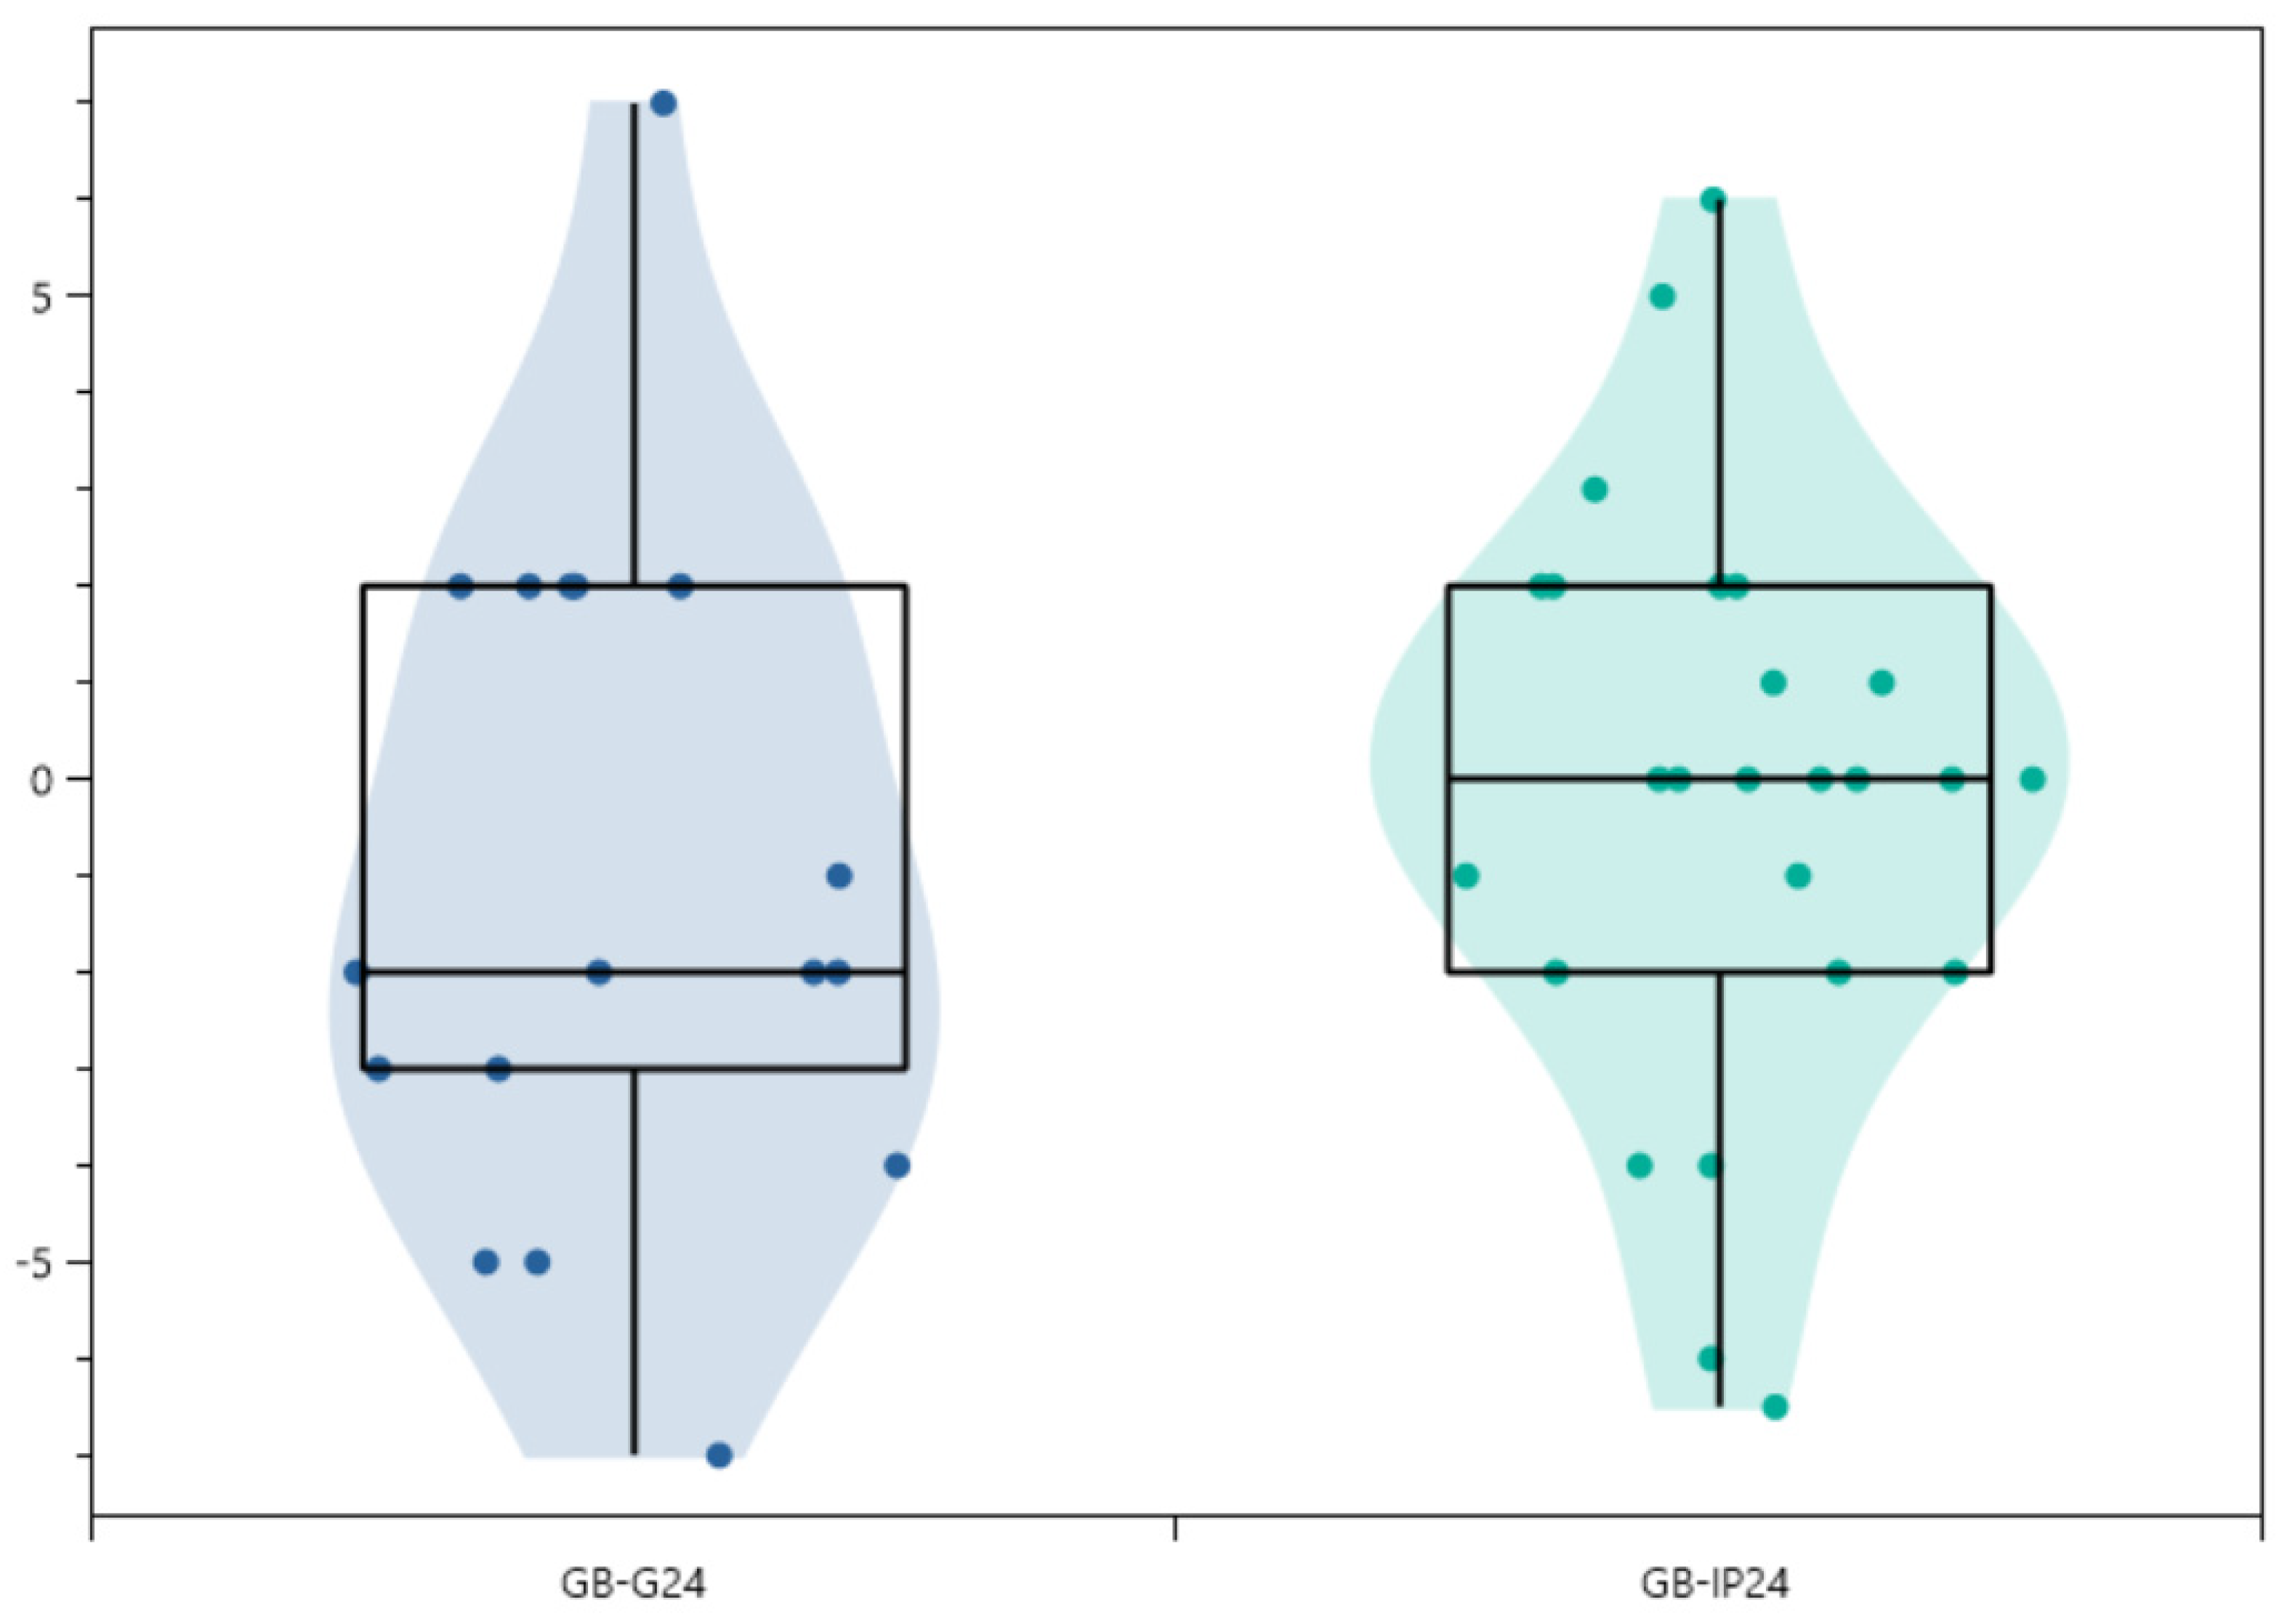

3.4. Radiographic Analysis

| Loss of correction | |||||||||

| 1st erect vs. 3/6 months (°) | −0.55 ± 3.32 (25) | [−8.0–5.0] | p = 0.874—NS | 0.00 ± 5.7 (2) | [−4.0–4.0] | p = 0.950—NS | −0.60 ± 3.25 (23) | [−8.0–5.0] | p = 0.773—NS |

| 1st erect vs. 24 months (°) | −0.65 ± 3.24 (42) | [−7.0–7.0] | p = 0.671—NS | −1.12 ± 3.52 (17) | [−7.0–7.0] | p = 0.685—NS | −0.18 ± 2.97 (25) | [−6.5–6.0] | p = 0.868—NS |